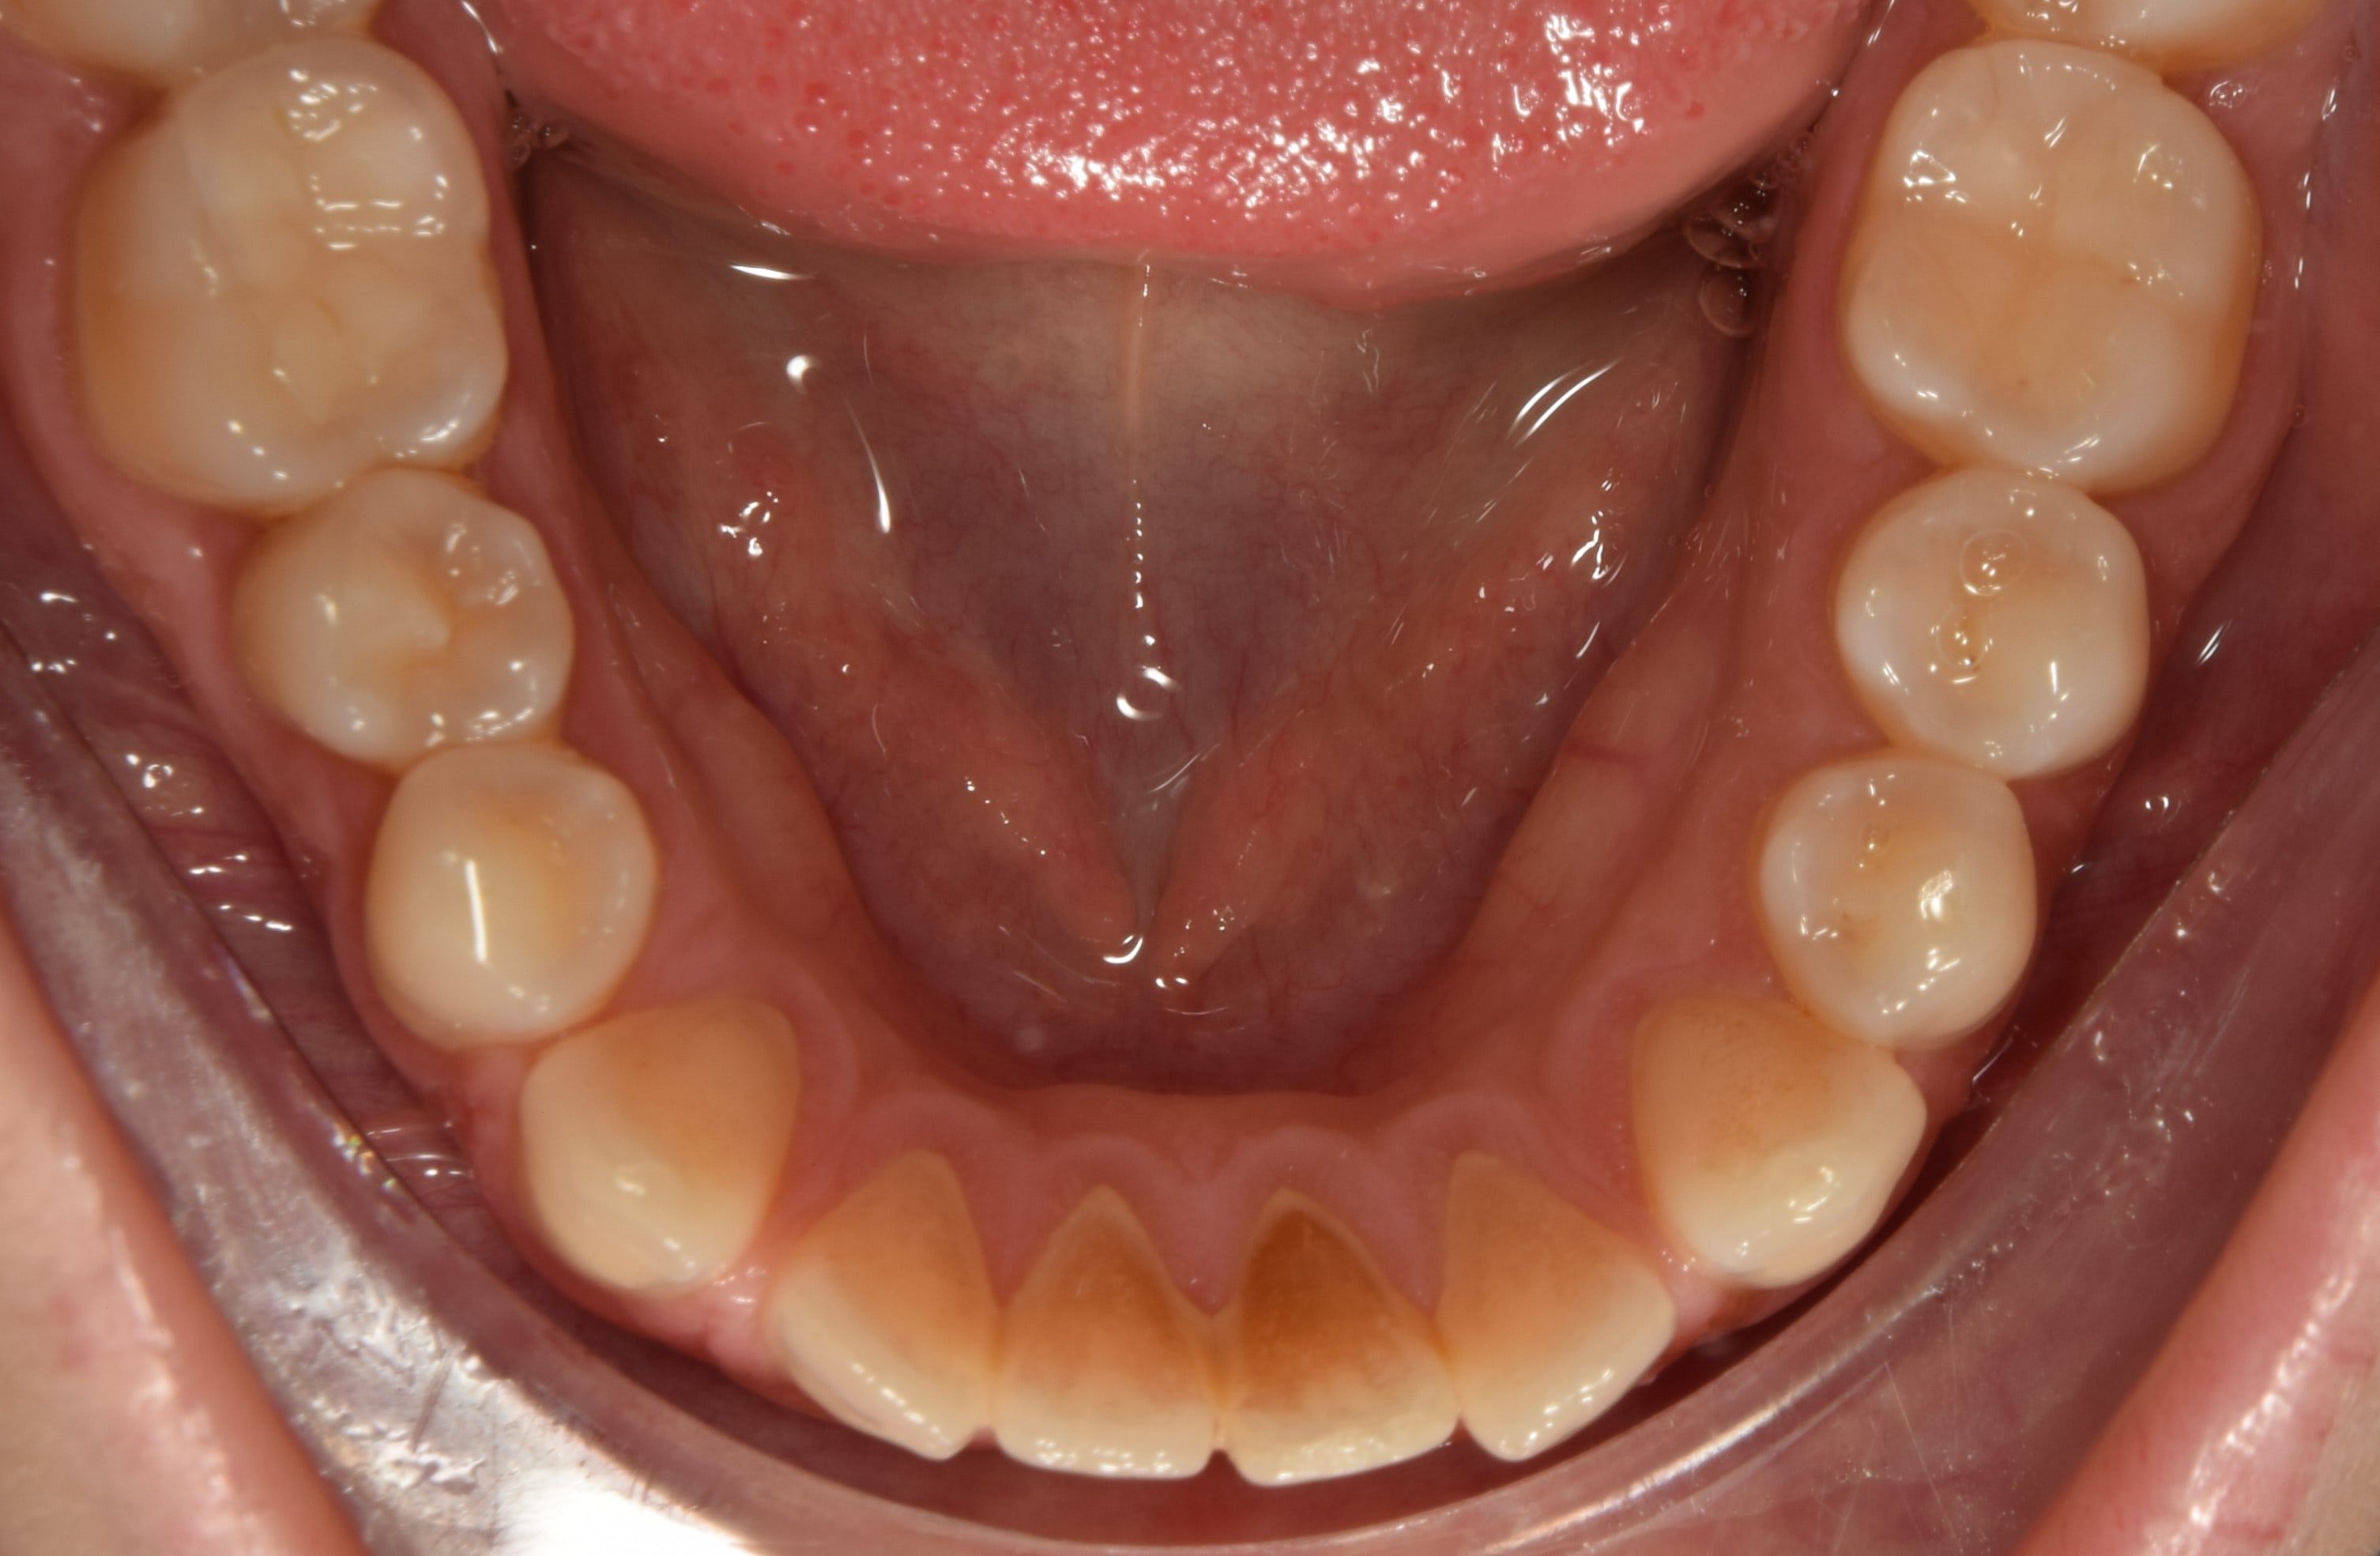

Késői vegyesfogazat

10-11 éves korban beszélünk késői vegyesfogazatról, amikor megkezdődik az oldalsó tejfogak elvesztése, és a tej őrlők, tejszemfogak helyére nőnek a maradó kisőrlők és szemfogak. Késői vegyesfogazatban a szájüregben eltérő sorrendben nőnek a maradófogak, illetve esnek ki a tejfogak.